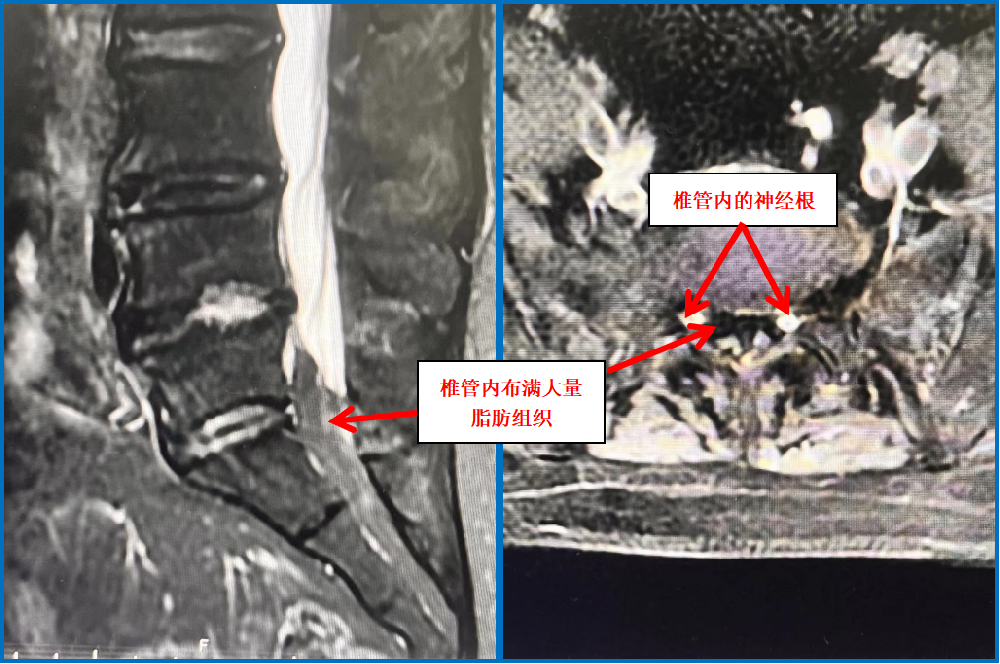

患者經(jīng)他人介紹來到我院脊柱外科門診就診,朱中蛟副主任通過患者的主訴及詳細(xì)的查體發(fā)現(xiàn)她存在間歇性跛行的表現(xiàn),腰椎過伸試驗(yàn)陽性,提示為典型的腰椎管狹窄的臨床表現(xiàn),但通過患者的腰椎CT,卻發(fā)現(xiàn)其不存在腰椎間盤突出或黃韌帶肥厚、骨性增生等情況,不存在腰椎管狹窄。但患者癥狀這么重,肯定有問題!細(xì)心的朱中蛟醫(yī)師建議患者完善核磁共振等檢查,發(fā)現(xiàn)她的椎管內(nèi)擠滿了脂肪,導(dǎo)致硬膜囊受壓變形成Y型。

原來,這是一種比較罕見的“特發(fā)性椎管內(nèi)硬膜外脂肪增多癥”。硬膜外脂肪增多癥(Spinal epidural lipomatosis, SLE)是指椎管內(nèi)硬膜外間隙正常脂肪組織的病理性增生。其原因是椎管內(nèi)脂肪填充,行走時(shí)黃韌帶皺褶,椎管內(nèi)靜脈充血導(dǎo)致椎管進(jìn)一步狹窄,壓迫了馬尾及神經(jīng)根所致。好發(fā)于男性,好發(fā)于胸段,其次為腰段。硬膜外脂肪增多癥常見的病因多與長期攝入外源性甾體類激素、激素異常疾病、肥胖癥等有關(guān)。

正常人的椎管內(nèi),都含有少量的脂肪組織。但該患者的腰椎管內(nèi)脂肪含量卻異常增多,對神經(jīng)產(chǎn)生了明顯的壓迫,因而出現(xiàn)相應(yīng)的神經(jīng)壓迫癥狀,嚴(yán)重影響了工作和生活,需要手術(shù)治療。但常規(guī)開放手術(shù)創(chuàng)傷大,并且患者體型肥胖,對手術(shù)暴露及切口愈合都有一定影響。朱中蛟帶領(lǐng)科室團(tuán)隊(duì)經(jīng)過認(rèn)真檢查、準(zhǔn)備,并與患者溝通后,決定通過UBE(單側(cè)雙通道脊柱內(nèi)鏡技術(shù))手術(shù)為患者解除病痛。